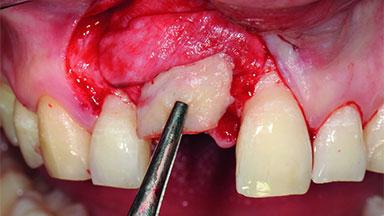

Bone Augmentation Horizontal|Simultaneous|Staged

Augmentation Materials Xenogenous|Membrane

Soft Tissue Grafting Simultaneous

Bone Volume Deficient horizontally, requiring prior grafting